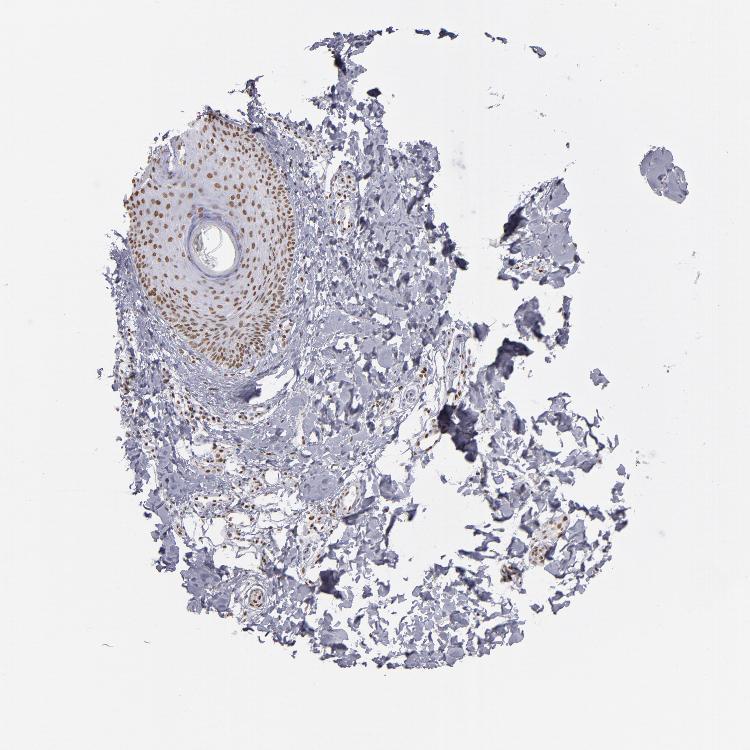

SKIN 2 - Antibody stainingi

Antibody staining in the annotated cell types in the current human tissue is reported as not detected, low, medium, or high, based on conventional immunohistochemistry profiling in selected tissues. This score is based on the combination of the staining intensity and fraction of stained cells.

Each image is clickable and will lead to virtual microscopy that enables deeper exploration of all samples and also displays staining intensity scores, fraction scores and subcellular localization as well as patient and tissue information for each sample.

Antibody HPA001907Antibody HPA002735Antibody CAB010451Antibody CAB080271

Epidermal cells MediumHighMediumHigh